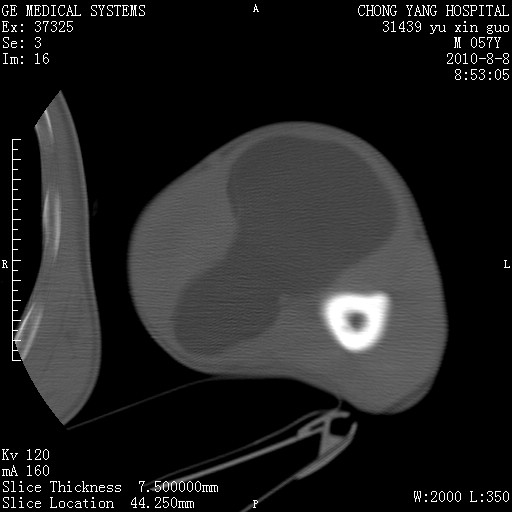

标题: CT28267:M57Y 上臂包块8年余。 [打印本页]

标题: CT28267:M57Y 上臂包块8年余。

典型脂肪瘤改变

上臂软组织内脂肪瘤。

包膜光滑、完整的脂肪密度肿块,支持脂肪瘤。

脂肪瘤。有ct值?